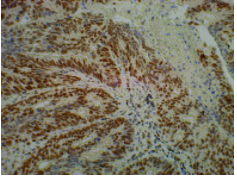

Appendix Cancer

![]()

Immunohistochemistry staining of paraffin-embedded human tumor tissue with mouse anti-MLH1 using product (ICP9988) as the 2nd antibody.